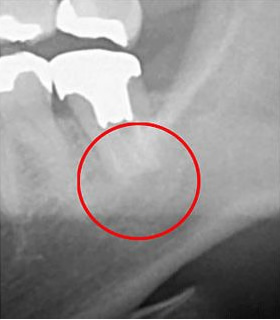

次の画像は、同じ患部をCTとレントゲンで撮影した画像です。

左の写真がCTで、右の画像がレントゲンで撮影したものです。

赤丸で囲んだところには、黒い影が見えます。ここには炎症が起こっているのですが、右の写真には影がありません。

つまり、レントゲン写真だけで診断すると、この炎症は見逃されてしまう可能性が高いということです。気がつかない間に炎症は悪化し、抜歯することになったかもしれません。当院は、このようなことを防ぐために、CTによる診断を徹底しています。